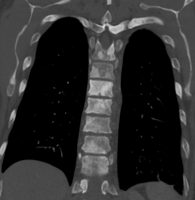

Prostate cancer that has metastasized to the lymph nodes

Prostate cancer that has metastasized to the bone